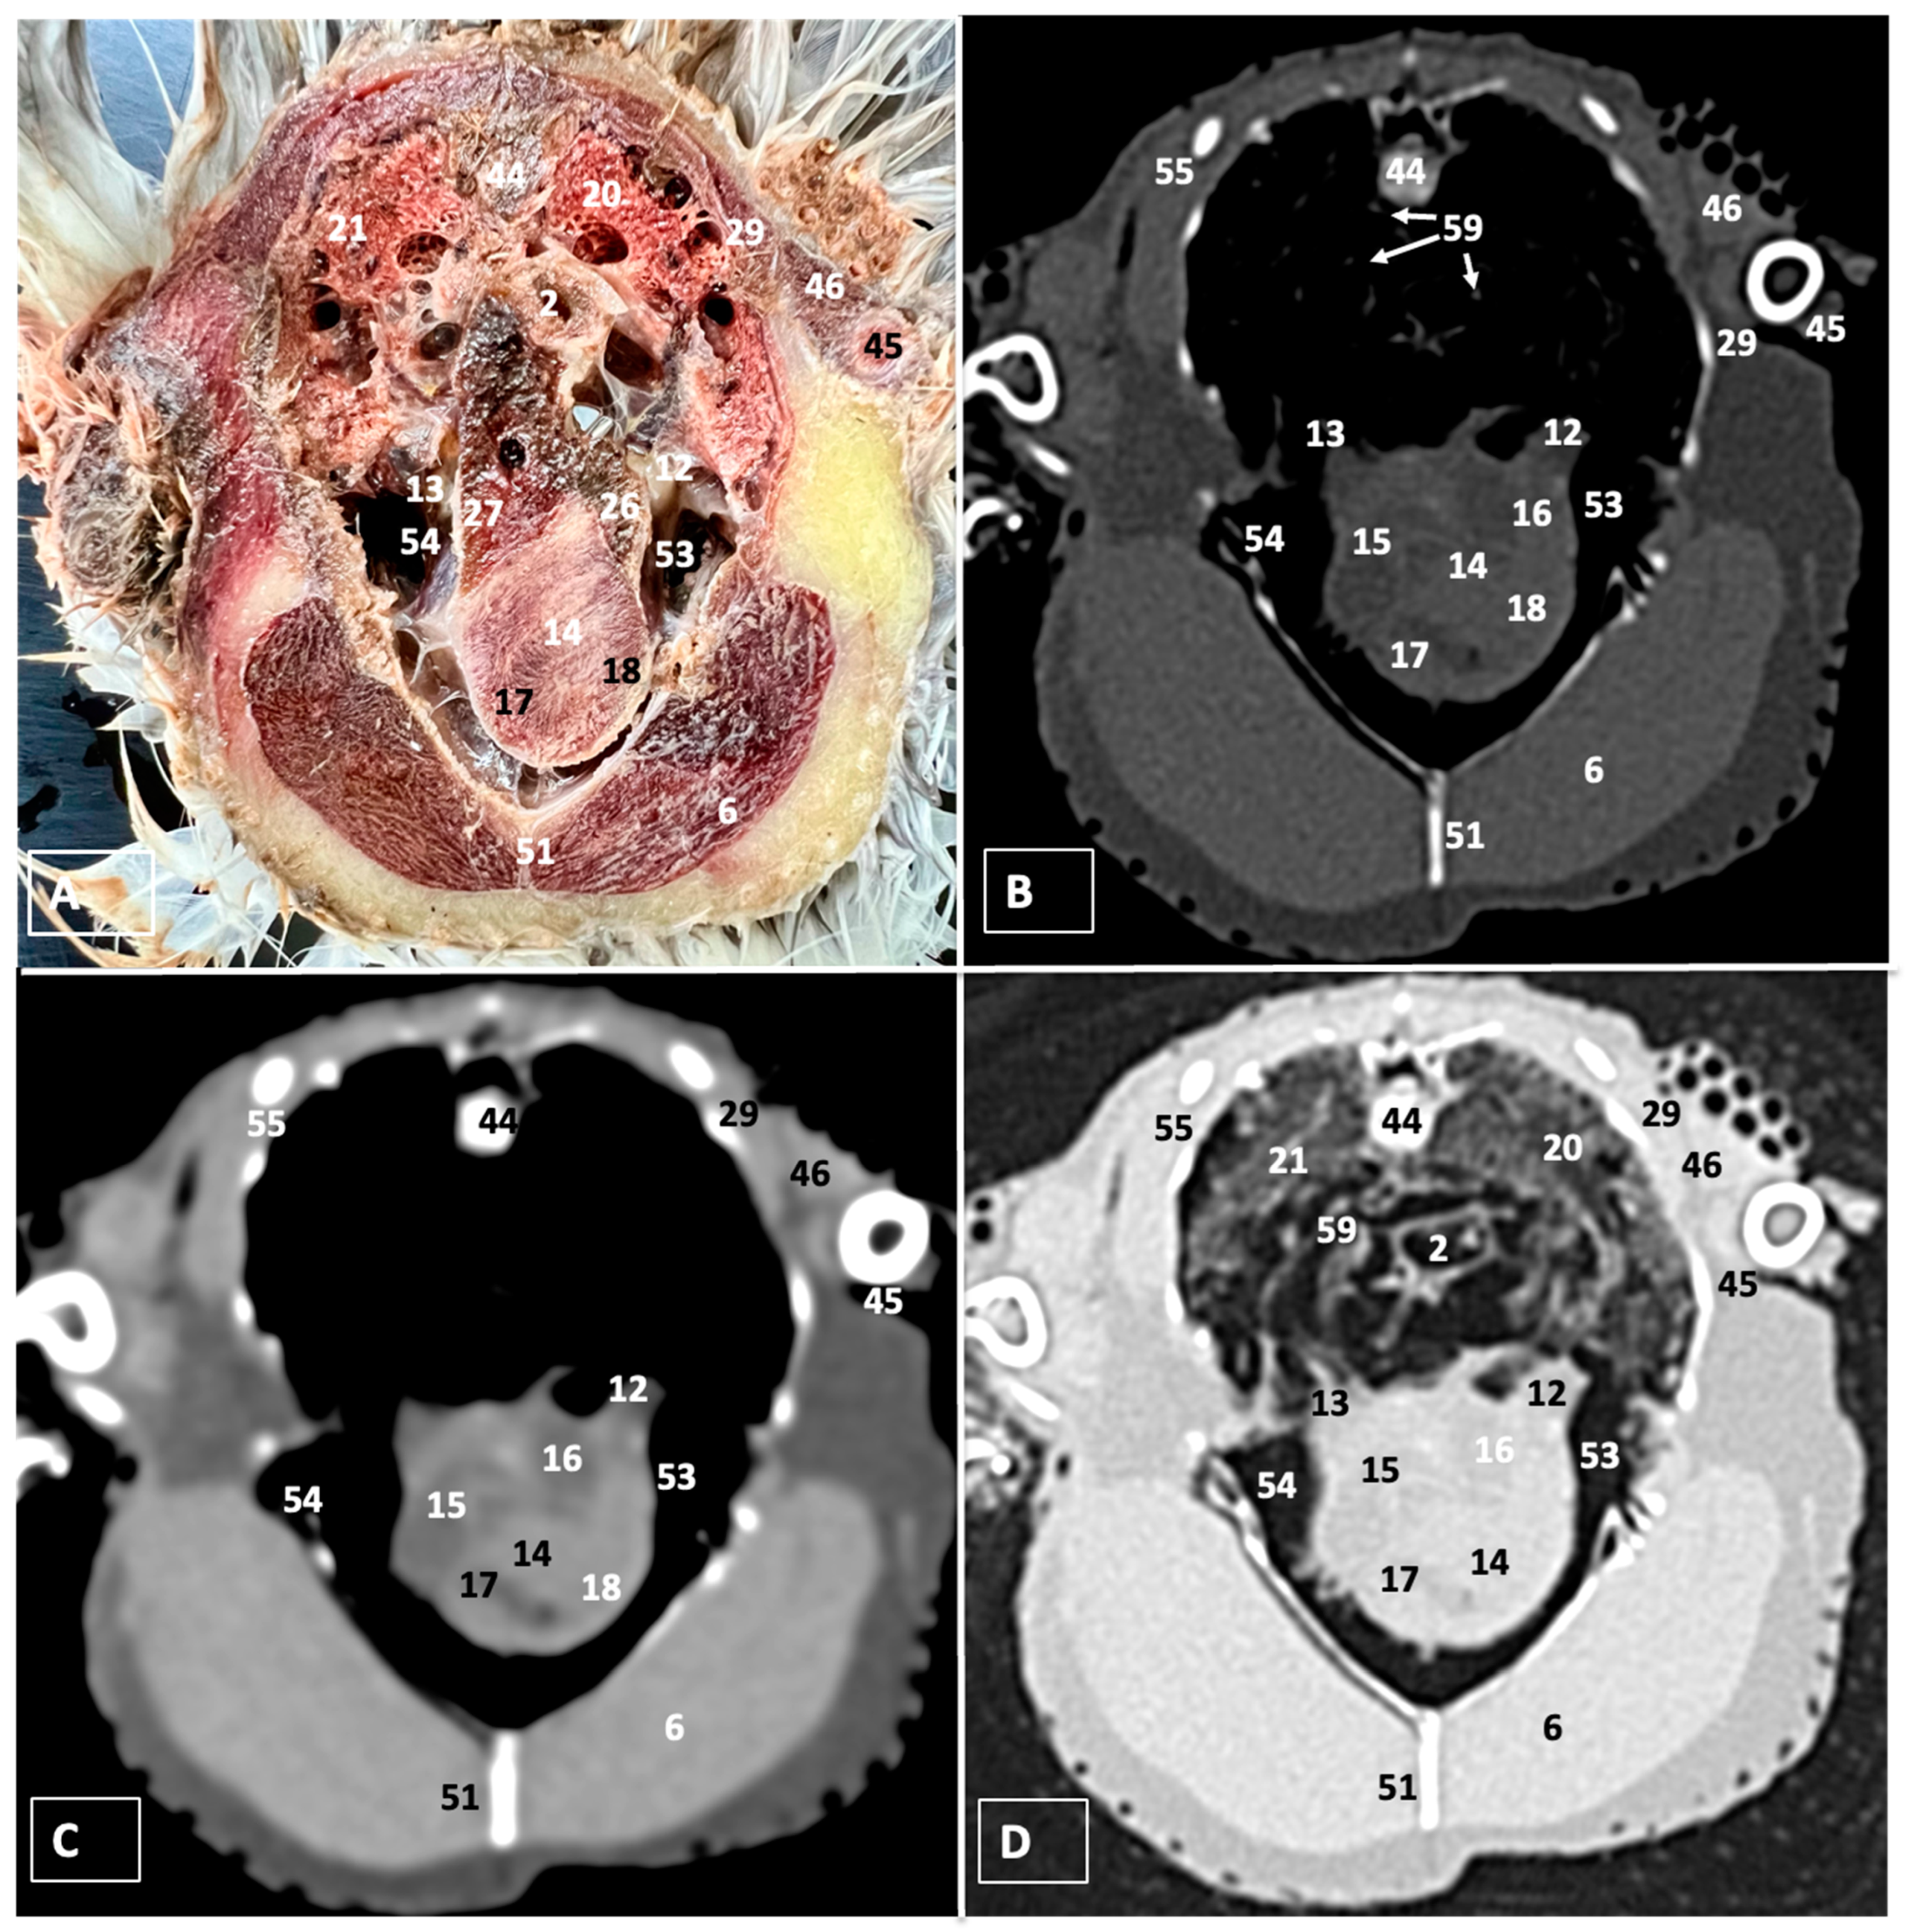

A Cadaveric Study Using Anatomical Cross-Section and Computed Tomography for the Coelomic Cavity in Juvenile Cory’s Shearwater (Aves, Procellariidae, Calonectris borealis)

3. Results

3.1. Anatomical Dissections and Cross-Sections

3.2. Computed Tomography Images